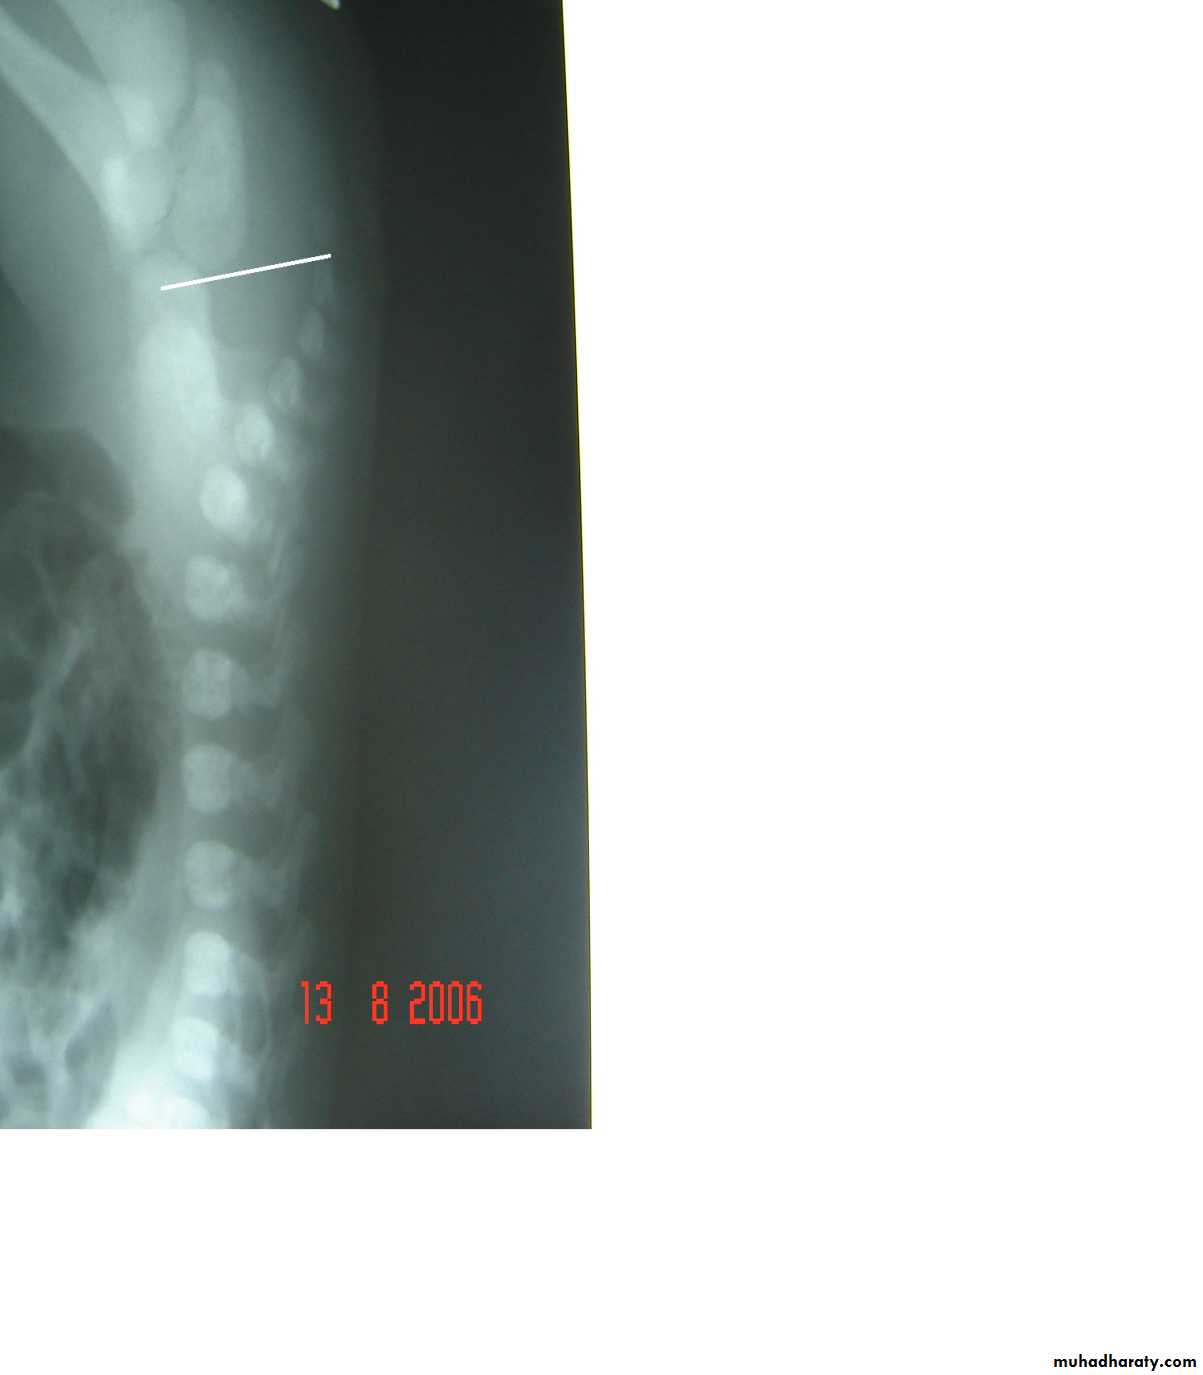

Second photo:

Diagnosis: congenital diaphragmatic hernia

Description: more dextrocardia – diaphragm not present – there is nasogastric tube

severe distress – very tired - 1 day age baby – more number of intestinal loops in

the chest - there is no lung tissue in the chest.

Treatment: pull the intestine ad close the hernia (through abdominal approach).